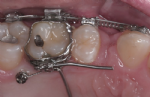

Verankerung – Miniimplantat

Im Rahmen der Behandlungsplanung wird die Richtung der Zahnbewegungen festgelegt. Um bestimmte Zahnbewegungen ohne unerwünschte Nebenwirkungen durchführen zu können, sind manchmal Verankerungen sinnvoll, die unabhängig von den Zähnen sind.

Besonders elegant ist dabei die Anbringung kleiner Pins neben den Zähnen oder im Bereich des Gaumens. Diese so genannten Mini-Implantate verankern sich zahnunabhängig im Kiefer und erlauben zielgerichtete Bewegungen. Die Behandlungszeit verkürzt sich entsprechend.